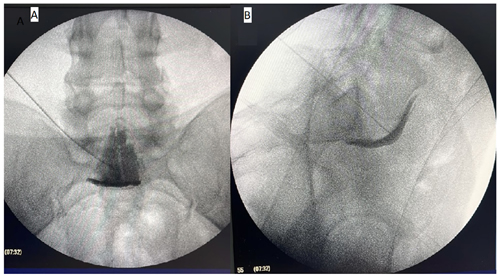

Materiales y métodos: En este estudio retrospectivo descriptivo, se analizaron 100 pacientes a los que se les realizó bloqueo del plexo hipogástrico superior guiado por fluoroscopia. Se obtuvo datos de dolor percibido y requerimiento de analgésicos a los 0, 1, 3 y 6 meses después el bloqueo, y se registraron las complicaciones como sangrado, infección, lesión neurológica, dolor persistente y toxicidad. La percepción del dolor se analizó mediante el modelo lineal generalizado con efectos mixtos para medidas repetidas.

Figura 1

Figura 2